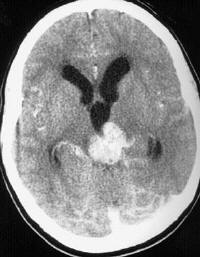

Refer to the picture above for question 1. |

1. The organisms responsible for the above appearance include: